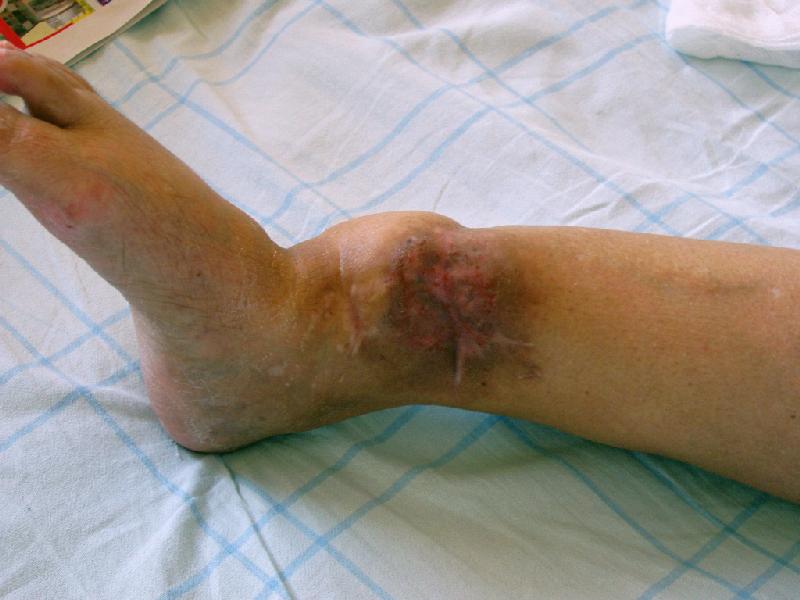

Глубокоуважаемые коллеги,Поступила женщина 72 лет. Полтора года назад - укушенная рана, перелом голени. Лечили аппаратом, не срослось. Долго не заживала рана.

Но вроде уже с полгода мягкие ткани закрыты. Спереди подпаянные рубцы. Есть приличная подвижность на уровне несращения. Картинки в приложении. Что предложите? Спсибо заранее.

If it was a dog bite and the wound have only healed one year after the open fracture, it was obviously infected. On this case, especially after a dog (or human!) bite, I would be preoccupied if I nail it.

Nevertheless I (and the patient too, if you explain the risks of a ORIF in this case) will be leaning to do an Ilizarov.